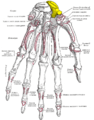

_01_palmar_view.png) Left hand anterior view (palmar view). Scaphoid bone shown in red. | |

Scaphoid bone. Scaphoid shown in yellow. Left hand. Palmar surface.

Scaphoid shown in yellow. Left hand. Palmar surface. Scaphoid shown in yellow. Left hand. Dorsal surface.